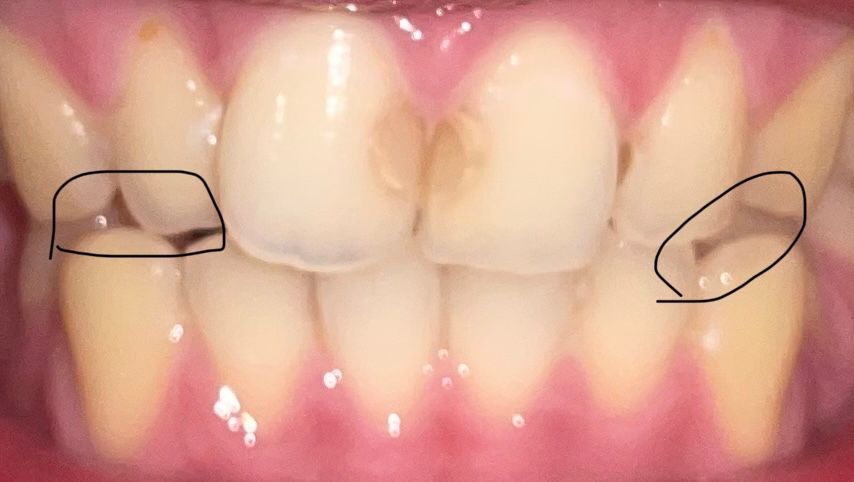

아래 치아 송곳니가 좀 많이 갈렸는데 옛날 사진이랑 비교해 봐도 티가 많이 납니다 빈공간도 생기고 치과가서 어떤 치료를 받아여 할까요 크라운을 씌워야 하나요?

해당되는 부위의 빈 공간은 치아의 비열의 문제인 것으로 보입니다 . 공간이 신경쓰인다면 보철치료를 받아서 공간을 메꿀 수 있습니다.

잇몸이 퇴축되고 치아가 마모되는 것은 교합이 문제일 가능성이 높으며

치아가 마모되지 않도록 교합을 조정할 필요가 있을 경우 조정하고 악습관을 바꿀 것 같습니다.

크라운이 필요한 치아는아닙니다.

송곳니는 교합(위아래 치아 맞물림)설정, 외모(심미)와 관련해서 굉장히 중요합니다

현재로선 송곳니가 마모가 다소 진행되었는데 이로 인해 교합이 망가져있을 수 있으므로 교합에 대한 평가 (특히 전방유도교합)가 필요하겠고 더하여 왜 마모가 되고 있는지 원인파악 후 개선이 필요하겠습니다

단순히 크라운 씌운다고 끝날 부분은 아닙니다 원인 파악후 크라운 씌우는 치료 진행해도 늦지는 않습니다

+ 참고로 앞니 충치는 치료할 필요성이 있는 정도입니다

치아가 마모된경우에는 증상이 없다면 그냥 지내셔도 크게 문제가 되지 않습니다. 사진은 마모된것보다는 무시는걸 다르게 해서 차이가 나는거 같습니다.

갈리고 닳은 치아 의 경우 마모 정도가 크지 않은 경우 크라운 보다는 레진으로 떼우는 치료가 가능합니다.